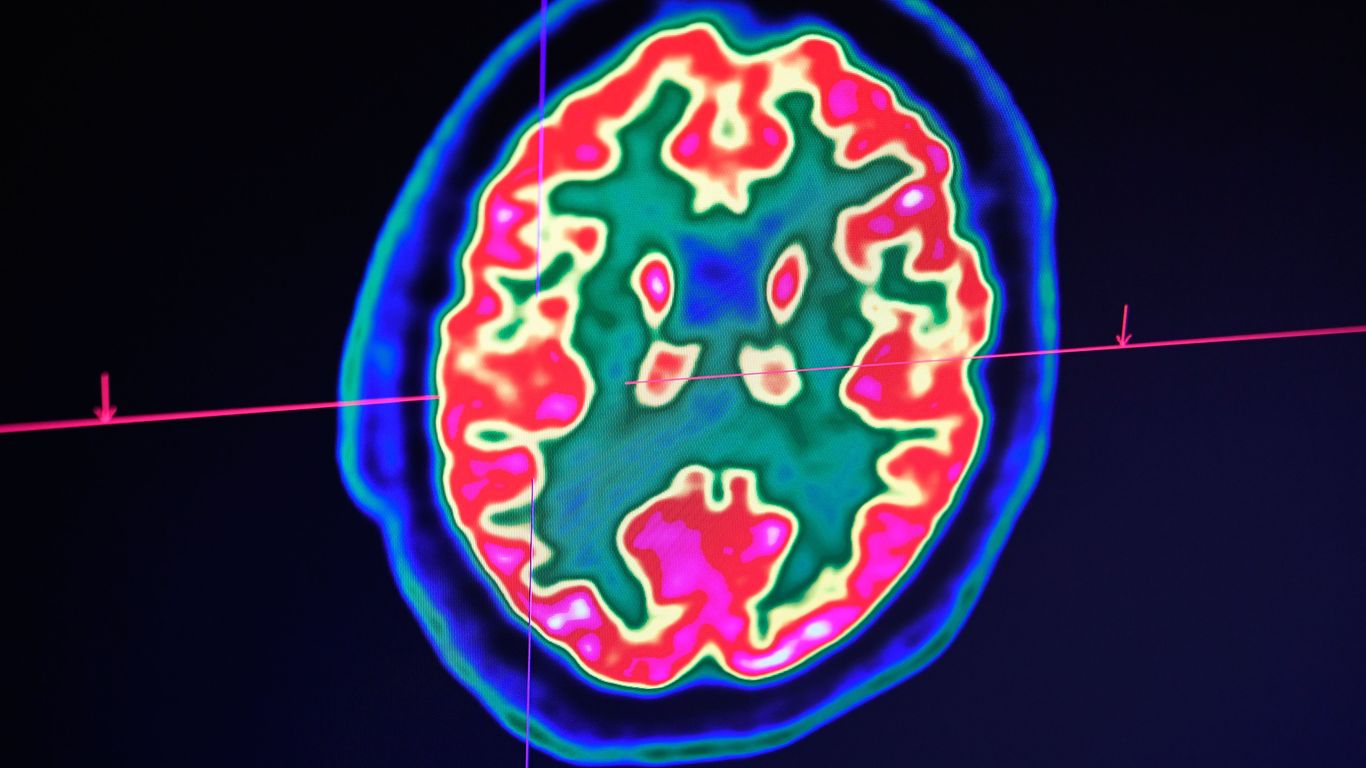

Details: Two microchip implants were inserted into the brain of a German patient, according to the study published by Ujwal Chaudhary and Niels Birbaumer. Afterward, the patient was able to form words and full sentences using mental impulses.